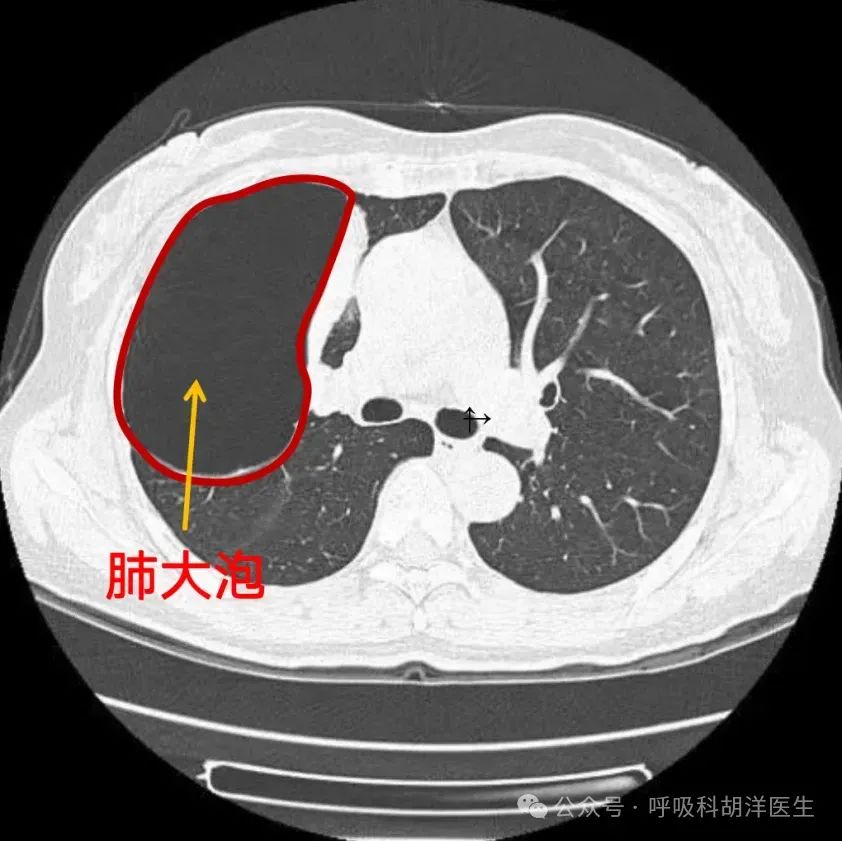

67面对巨大肺大疱呼吸科医生该如何处理

面对巨大肺大疱呼吸科医生该如何处理